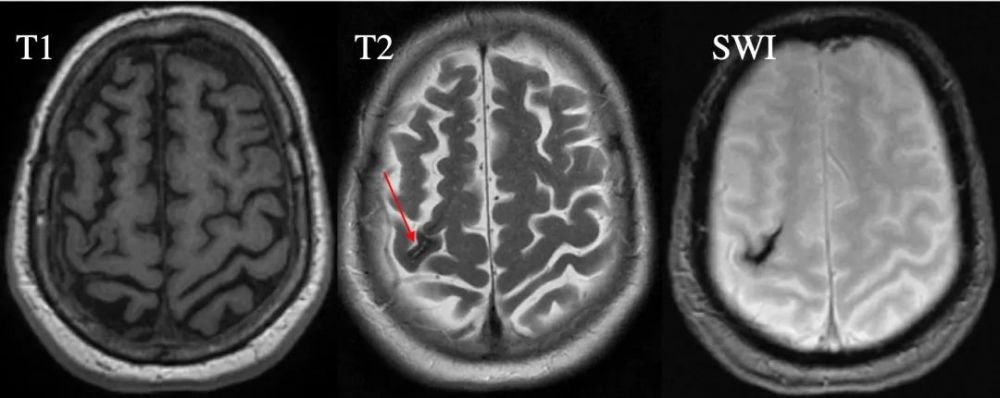

血肿逐渐吸收或液化 , 中心形成腔隙 , 由液体充填 , 呈长T1长T2信号;含铁血黄素则沉积于腔壁 , 在T2像上出现低信号环(图7,红箭) , 为慢性血肿的特征性影像表现 。

图7 80岁女性 , 右侧顶叶出血4年 。 (Radiopaedia , by Dr Roberto Schubert)